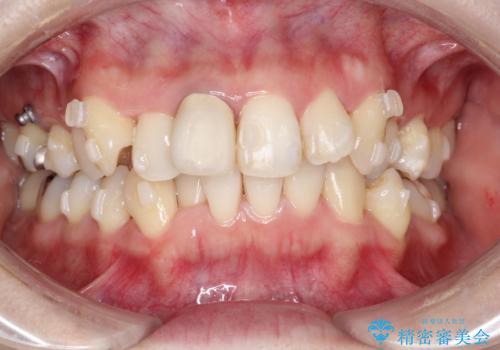

上下のガタガタのマウスピースによる非抜歯矯正

- 上下のがたつきを主訴に来院された患者様です。

上下の前歯と奥歯にがたつきがありました。

上下の奥歯を後方に移動させるのと、歯と歯の間をわずかに削ることでスペースを作り、歯を並べる計画としました。

インビザラインにて治療を行いました。

比較的がたがたの度合いが大きかったですが、しっかりとマウスピースを使用していただけたので、順調に治療を終えることができました。